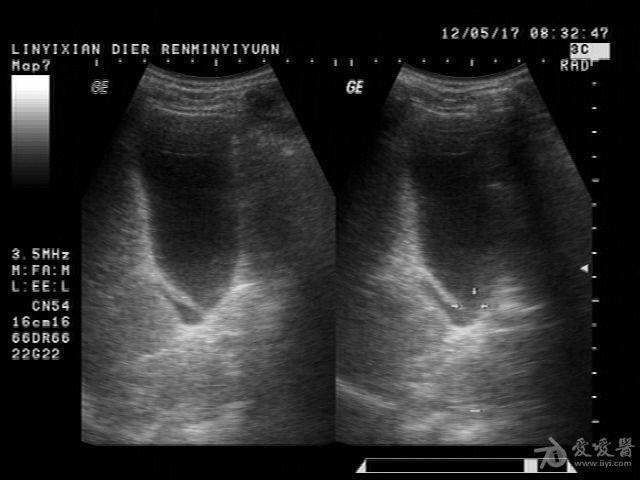

患者男性,57岁,十多年前曾患“肝炎”,近一年在它院曾诊断为:肝硬化。一月前在市医院治疗发现有腹水形成并发现有“腔梗”。古来我院就诊。B超提示:肝脏病理声像(肝光点增粗、肝硬化声像)胆囊图像如图。腹盆腔未及游离暗区回声。

这个胆囊颈部的暗区可以称“胆囊憩室”吗?

邹褶吧,不是憩室

很明显的胆囊皱褶,这种现象应该很常见的,肝硬化的时候胆囊比正常要大些

应该是胆囊皱褶。